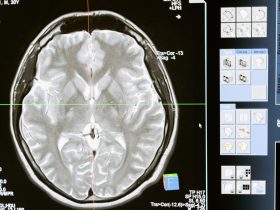

Angin ahmar akan menyebabkan sel otak kekurangan oksigen dan ianya boleh tercedera atau mati hanya dalam tempoh beberapa minit sahaja.

Epilepsi atau sawan babi merupakan gangguan yang menyebabkan serangan sawan berkala yang berlaku apabila impuls elektrik otak terganggu.